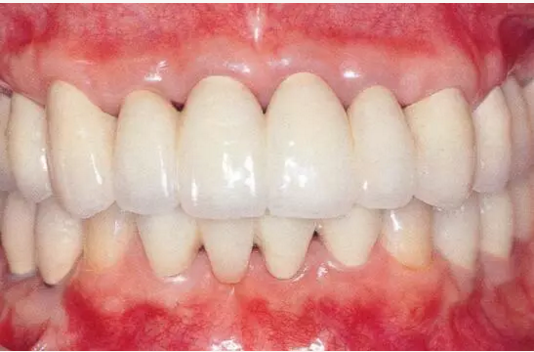

33333.png

▲圖19-13

佩戴最終修復(fù)體時(shí)的正面照片。

333333.png

▲圖19-14

佩戴最終修復(fù)體時(shí)的X光片。骨邊緣水平平坦,探診值維持在1~2mm。